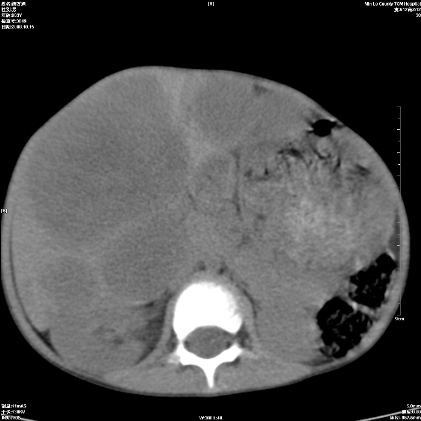

标题: PED1609:男性,3岁。彩超示肝Ca. [打印本页]

标题: PED1609:男性,3岁。彩超示肝Ca.

3岁;肝低密度灶;有钙化;有转移灶;考虑肝母细胞瘤;查afp

支持肝母细胞瘤肝内转移

考虑神经母细胞瘤并肝转移

考虑:1、右侧后下纵隔畸胎瘤。

2、肝脏多发血管内皮细胞瘤。

建议:增强确诊。